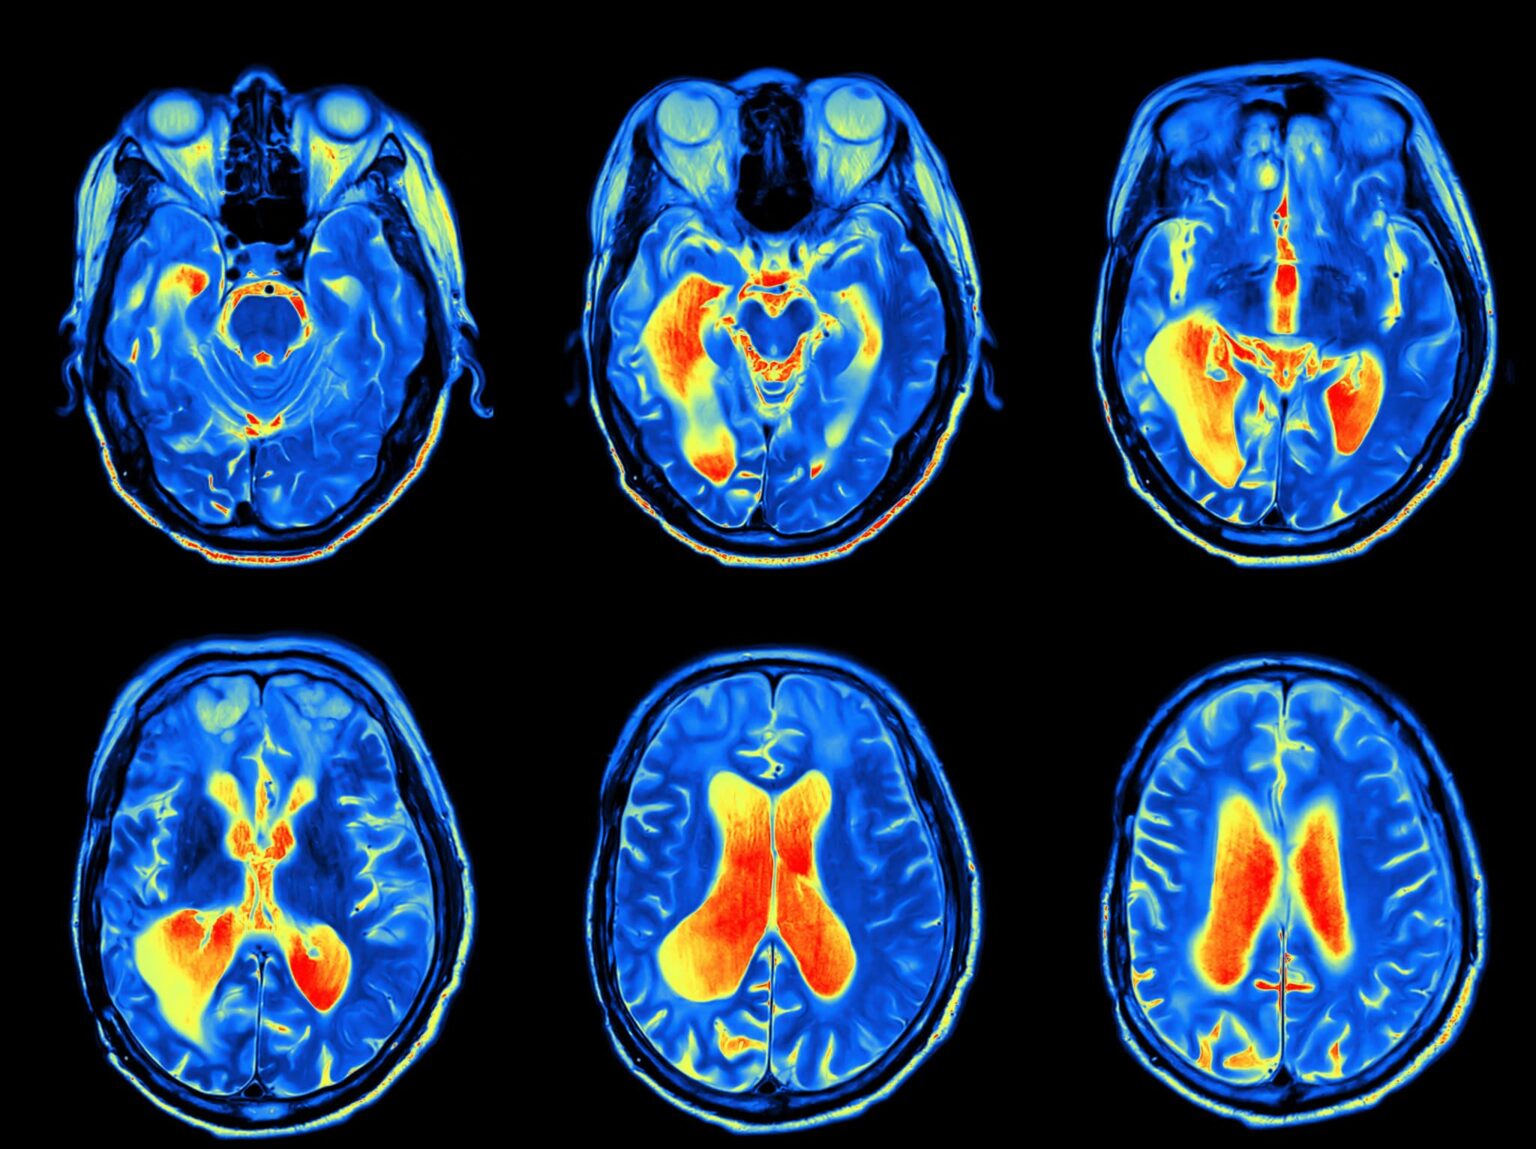

Our otolaryngologist will begin by discussing your symptoms and their impact on your daily life and performing physical and neurological examinations. They may also perform a CT scan, MRI, bone scan and positron emission tomography (PET) scan.